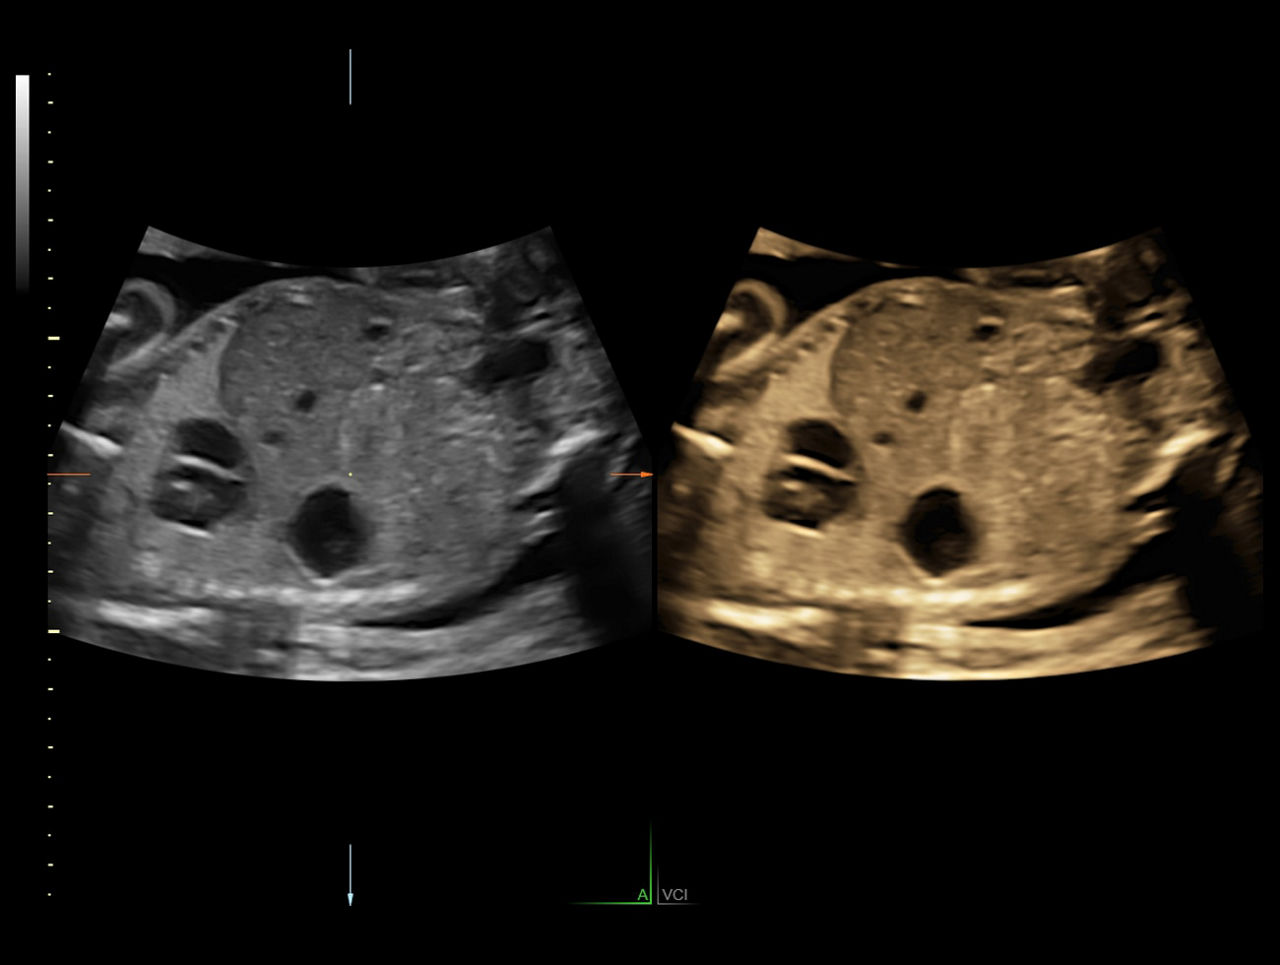

Volume Contrast Imaging (VCI)

Adjusts slice thickness on 3D or 4D images to help enhance contrast resolution using bone and tissue rendering techniques.